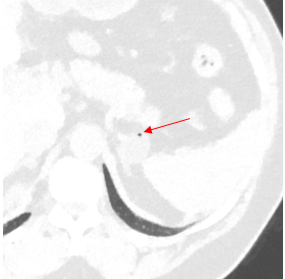

Attention to #spectral images! Gopal Punjabi ⚠️ The endobronchial content is enhancing --> solid! 1️⃣Virtual non-contrast (VNC)= 39HU 2️⃣Conventional= 71UH (>20UH compared to VNC) 3️⃣ Iodine density =1.26 mg/ml